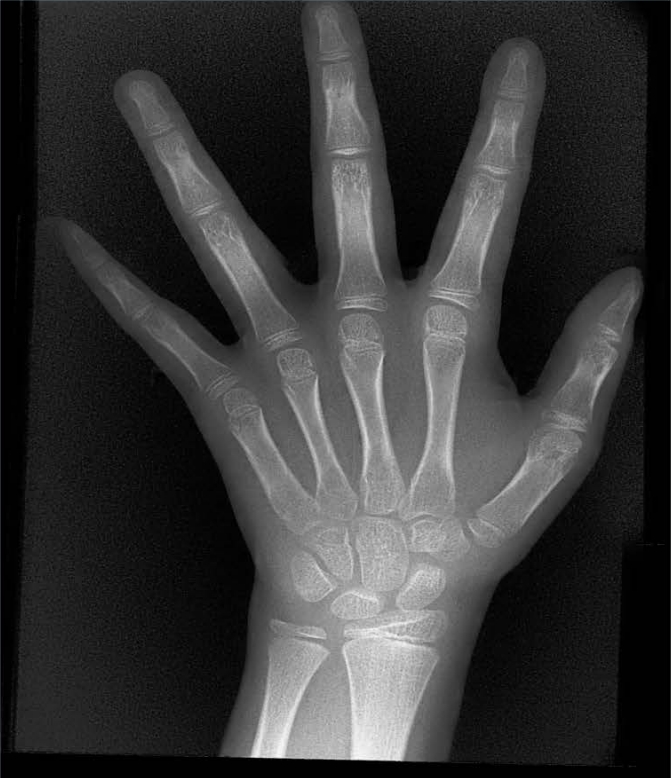

骨齡是反映兒童真實生長發(fā)育水平的關鍵指標,為相關疾病診療提供重要支撐。它可助力身高異常疾病病因診斷,支撐矮小癥等治療的監(jiān)護與療效評估,還能精準評估生長發(fā)育及青春期突增狀況,為早期干預提供依據(jù)。

X射線骨齡儀適用于兒童保健科、內(nèi)分泌科、兒科等多個臨床科室,可滿足不同年齡段兒童的骨齡檢測需求。無論是常規(guī)生長發(fā)育評估、身高異常篩查,還是疾病治療后的療效監(jiān)測,其檢測結(jié)果都能為臨床診療提供標準化、可對比的科學數(shù)據(jù),助力醫(yī)療機構(gòu)提升診療規(guī)范化水平。